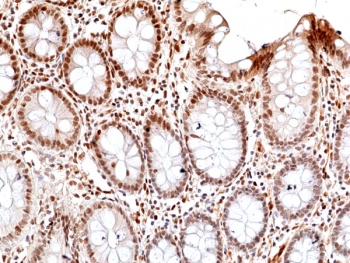

This antibody reacts to human JNK1, JNK2, and JNK3 only when phosphorylated at Thr183 and Tyr185.

The stated application concentrations are suggested starting points. Titration of the recombinant phosphorylated JNK antibody may be required due to differences in protocols and secondary/substrate sensitivity.

A phospho-peptide corresponding to human Phospho-JNK1/2/3 (Thr183/Tyr185) was used as the immunogen for the recombinant phosphorylated JNK antibody.